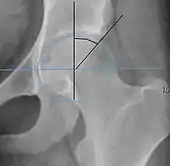

- (A) Hilgenreiner line, connects the inferior tips of the iliac bones,[4] at the triradiate cartilage. This line is used to measure the acetabular angle and as a reference for Perkin line.

- (B) Perkin line is perpendicular to Hilgenreiner line, touching the lateral margin of the acetabular roof.[5] This leads to four quadrants and a normal femoral head has to be located in the inferomedial quadrant. We can measure the lateral displacement of the femoral head with regard to the Perkin line by dividing the width of the head that crosses the Perkin line by the diameter of the head. The value for patients under 3 years must be 0 and in older children this ranges from 0 to 22%.